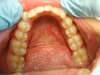

Nos Cas Cliniques orthodontiques 1

Photos avant traitement